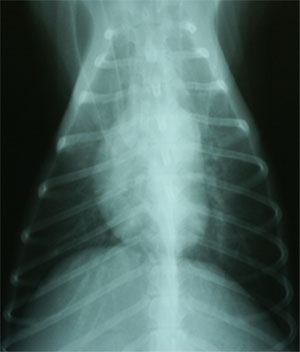

胸部X線所見:びまん性肺胞浸潤影(図1)。心陰影に形状異常なし(VHS=10.8, CTR=0.48)

図1 初診時胸部X線DV像。びまん性肺胞浸潤影がみられた。このときPao2 44 mmHgと重度の低酸素血症を示した。

血液ガス分析所見:pHa 7.50, Paco2 23 mmHg, Pao2 44 mmHg, [HCO3-] 18 mmol/L, A-aDo2 78 mmHg, P/F=210で、重度な低酸素血症を伴った慢性呼吸性アルカローシス